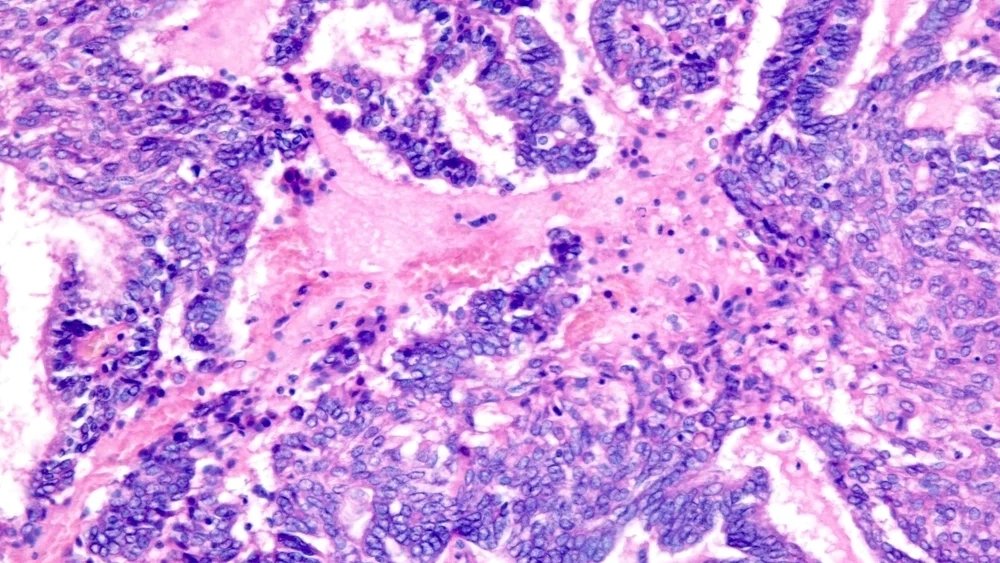

وتعتمد هذه الطريقة على حقيقة أن الريبوفلافين يرتبط بالحمض النووي والحمض النووي الريبوزي (RNA)، وعند تعريضه للأشعة فوق البنفسجية، فإنه يدمر المادة الوراثية للفيروسات والبكتيريا والطفيليات، مما يحرمها من القدرة على التكاثر. جاءت فكرة الاستخدام لعلاج الأورام من الكيميائي راي جودريتش في جامعة ولاية كولورادو. ولاحظ أنه بعد العلاج بالأشعة فوق البنفسجية، تفقد الخلايا قدرتها على الانقسام، لكنها تحتفظ ببنيتها.

ووفقاً لخطته، يمكن تحويل الخلايا السرطانية “المعطلة” لدى المريض إلى لقاح شخصي: فهي لا تشكل ورماً، ولكنها تحتوي على جميع المستضدات الجديدة – بروتينات الورم الفريدة التي يتعرف عليها الجهاز المناعي.

سيتم إجراء المرحلة الأولى من التجارب السريرية في مركز مدينة الأمل الطبي (كاليفورنيا). وتخطط الدراسة لتشمل ثمانية مرضى يعانون من سرطان المبيض المتكرر. بعد الاستئصال الجراحي للورم، ستتم معالجة الخلايا بالريبوفلافين والأشعة فوق البنفسجية، ممزوجة بمادة مساعدة محفزة للمناعة، ويتم إعطاؤها على ثلاث جرعات من اللقاح. الهدف الرئيسي هو تقييم السلامة والاستجابة المناعية.